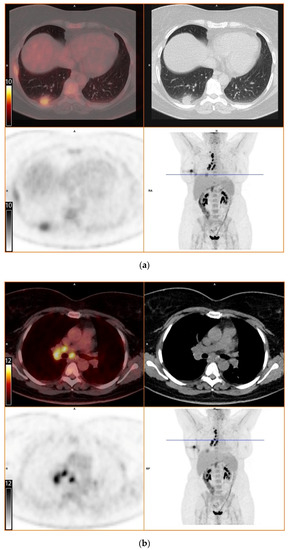

To further evaluate the suspected malignant disease, a [18F]FDG-PET/CT was performed (day +14). It detected multiple hypermetabolic lymph nodes of up to 33 mm in diameter, located right interlobar, at the right hilus, the mediastinum and right supraclavicular. The previously known lesion of the right lung showed only moderate metabolic activity. In addition, a moderately active precaval lymph node was detected (Figure 1).

Figure 1.

[18F]FDG-PET/CT. Upper left: PET and CT fusion images. Upper right: CT images. Lower left: PET images. Lower right: Maximum intensity projection. Blue line: Axial imaging level. Scale bars: Standardized uptake value. Star: Postinterventional diffuse uptake of the right thoracic wall after chest tube placement. (a) Moderate uptake in a solitary solid pulmonary lesion with irregular margins in the right lower lobe of the lung (b) Greater uptake in the draining lymph nodes right interlobar, right hilar and mediastinal (c) A further draining right supraclavicular lymph node showing high uptake as well (d) Moderate uptake in a precaval abdominal lymph node.